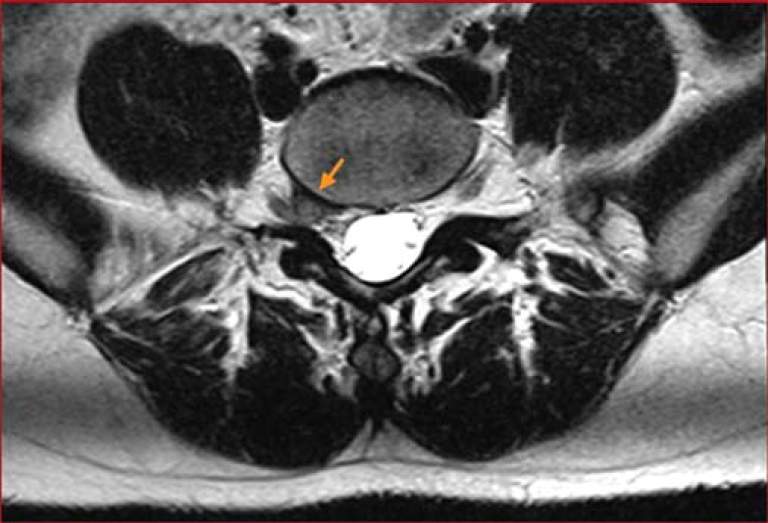

Dr. Geraci, along with Laura Favaro PT, DPT & Ryan G. Boggs PT, DPT had an article entitled Conservative Managment of a Foraminal Lumbar Disc Herniation published in Musculoskeletal Imaging February 2021.